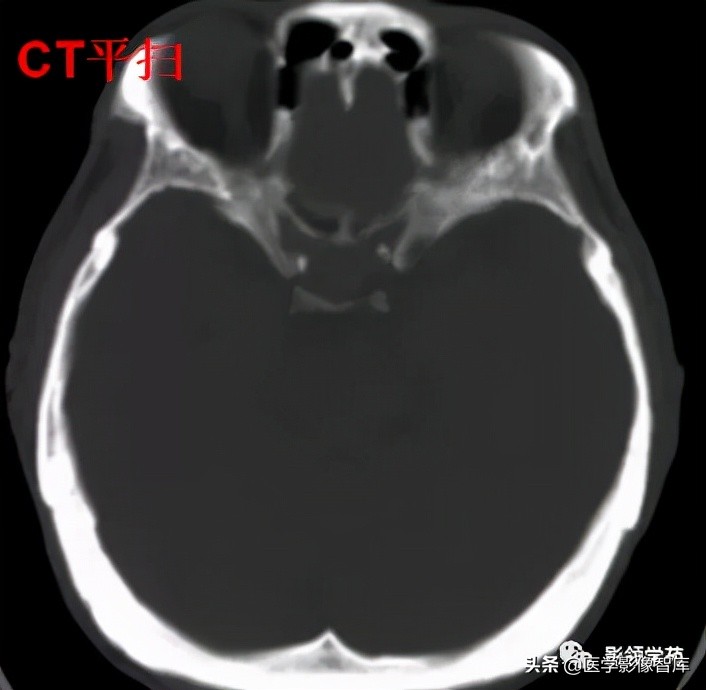

女 72岁,发现糖尿病3年余

鞍上区见一团块状稍高密度影,边界尚清,密度均匀。

鞍上右上方见一类椭圆形流空影。

病灶明显强化(瘤内血栓未强化),边界清楚,与右侧颈内动脉海绵段分界不清。垂体大小、形态未见异常。